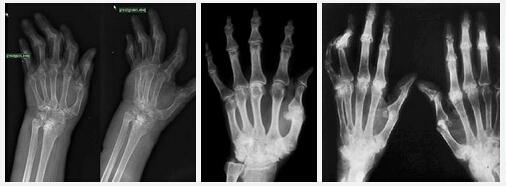

风湿性枢纽关头炎是一种反常反馈性疾病,受累的枢纽关头主要是膝、踝、肩、肘、腕等大关节,这样的疾病痛苦悲伤起来会很让人受不了的,而且还会频频发作,在凛凛的时令如许的痛苦悲伤会变得愈加敏锐,于是风湿性枢纽关头炎应做好预防与管束。哪些办法梗概防控风湿性关节炎病情恶化?

对付风湿性关节炎,朋友们还需要留心饮食有节、起居有常,这是强身保健的首要步伐。一旦患优势湿性关节炎不迭时治疗会构成很老火的终归,并且惹起很多并发症,后来会招致枢纽关头正常病变。